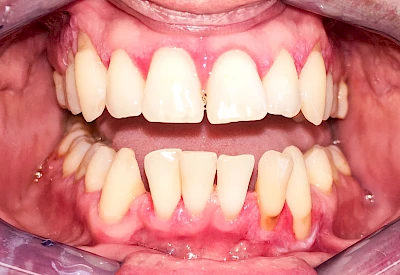

Ist zunächst nur das Zahnfleisch von der Entzündung betroffen, spricht man von Gingivitis. Später, wenn auch der Knochen um die Zähne herum entzündet ist, spricht man von einer Parodontitis. Bei der Parodontitis wird der Knochen nach und nach abgebaut und das Zahnfleisch zieht sich zurück. Die Zahnhälse und Zahnwurzeloberflächen liegen mehr und mehr frei. Die Zähne werden zunehmend lockerer und fallen schließlich aus.

Bei Schwellung, Rötung oder Blutung des Zahnfleisches sollte neben der Intensivierung und Optimierung der Mundhyiene der Zahnarzt kontaktiert werden.